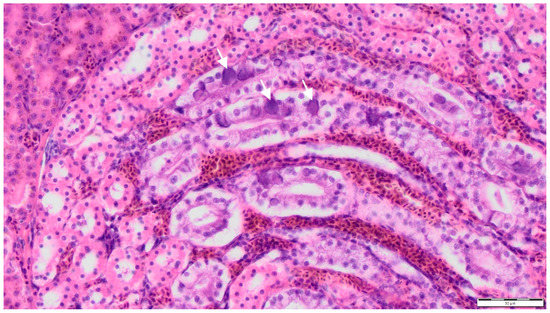

The nodules from birds with case nos. 1, 2, 4, 6 were characterized histopathologically by diffuse foamy and cholesterol-laden macrophages, multifocal fibrinous granulomas, central necrosis and fibrin, surrounded by multinucleated giant cells, histiocytes, lymphocytes and heterophils as well as various degrees of fibroplasia. Ziehl–Neelsen, Fite-Faraco, Von Kossa and Kongo red stains as well as PAS reaction were without additional findings, thus identifying these lesions as xanthogranulomatous inflammations [27,34] (Figure 3). In all six birds, large eosinophilic intranuclear inclusion bodies were documented in the epithelial cells of the collecting ducts of the kidney (Figure 4), regardless of the diagnosis of xanthogranulomas, which were present in four birds only. Additional findings in birds with xanthogranulomas (case nos. 1, 2, 4, 6) were splenic and renal haemosiderin in case no. 1, and subacute fibrinous conjunctivitis with isolation of Pseudomonas aeruginosa in case no. 6 (Table 1). The main histopathological findings in both birds without xanthogranulomas (case nos. 3, 5), in addition to viral nephritis, in case no. 3, comprised disseminated intravasal coagulation, necrotizing splenohepatitis with amphophilic intranuclear inclusion bodies inside reticular cells and hepatocytes, lymphocytic depletion of the lymph follicles of the spleen, acute catarrhal duodenitis, subacute ulcerative proventriculitis and subacute fibrinous fungal pneumonia, and in case no. 5, hepatic steatosis (Table 1).

Figure 4. Micrograph of a kidney from a Red-crowned Parakeet (Cyanoramphus novaezelandiae) labelled as case no. 1 with large eosinophilic intranuclear inclusion bodies (white arrows) in the epithelial cells of the collecting ducts. Haematoxylin and eosin staining, 400× magnification.